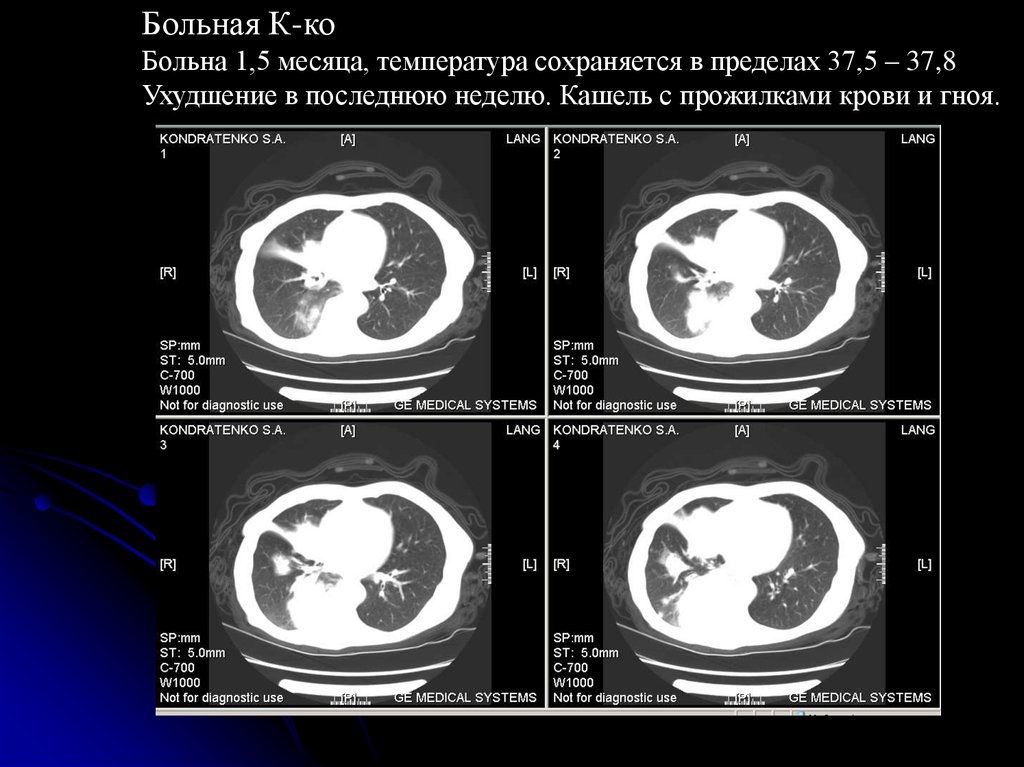

Больная К-ко

Больна 1,5 месяца, температура сохраняется в пределах 37,5 – 37,8

Ухудшение в последнюю неделю. Кашель с прожилками крови и гноя.